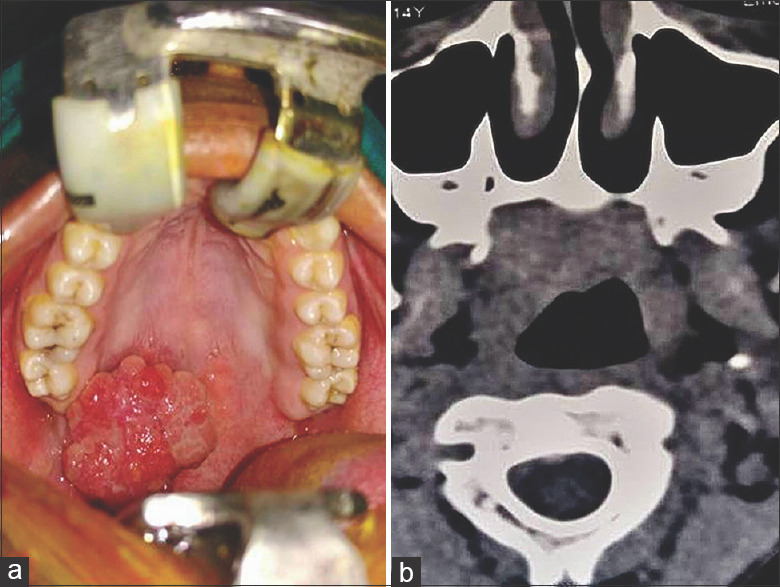

多形性腺瘤是大、小唾液腺最常见的良性肿瘤。组织学多样性是多形性腺瘤的特征。广泛的鳞状皮化生伴角蛋白填充的囊肿很少报道。我们在此报告两例涎腺多形性腺瘤伴增生鳞状化生及角蛋白填充囊肿的病例,并讨论其潜在的诊断缺陷。

Pleomorphic adenoma is the most common benign tumour of major or minor salivary glands. Histological diversity is the hallmark of pleomorphic adenoma. Extensive squamous metaplasia with keratin-filled cysts is rarely reported. Here we present two cases of pleomorphic adenoma with exuberant squamous metaplasia and keratin filled cysts formation in a minor salivary gland and discuss its potential diagnostic pitfalls.